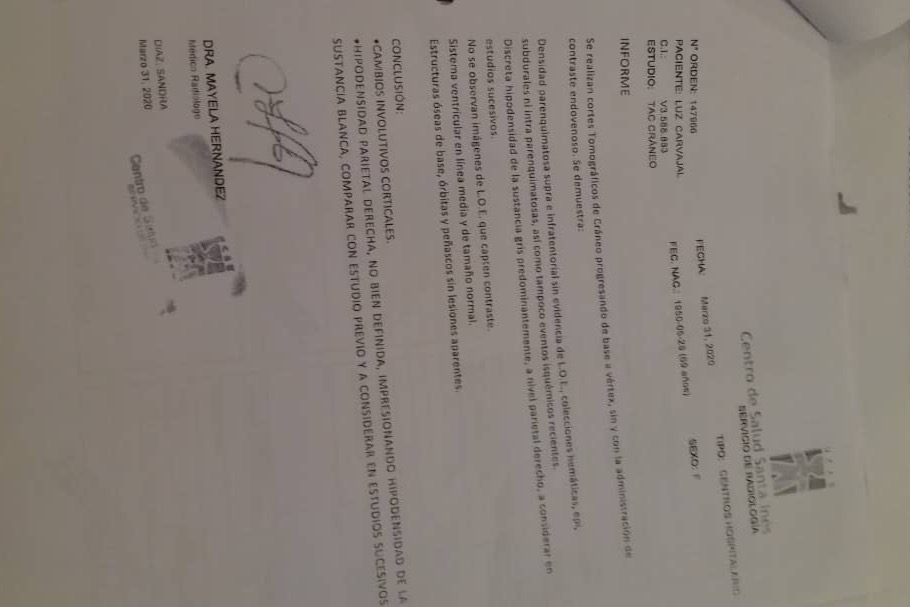

En septiembre de 2019 fue diagnosticada con cáncer de pulmón con una Lesión Ocupante de Espacio (LOE) de 2,5 cm y otra lesión en el Mediastino de 5,4 x 4,7 cm.

A continuación les dejo el diagnóstico, los exámenes, y los presupuestos de los próximos exámenes que hay que hacerle a mi mamá.

In September 2019, she was diagnosed with lung cancer with a Space Occupying Injury (LOE) of 2.5 cm and another lesion in the Mediastinum of 5.4 x 4.7 cm.

Down here I leave the diagnosis, exams, and budgets for the next exams to be done to my mom.

En septiembre de 2019 fue diagnosticada con cáncer de pulmón con una Lesión Ocupante de Espacio (LOE) de 2,5 cm y otra lesión en el Mediastino de 5,4 x 4,7 cm.

A continuación les dejo el diagnóstico, los exámenes, y los presupuestos de los próximos exámenes que hay que hacerle a mi mamá.

In September 2019, she was diagnosed with lung cancer with a Space Occupying Injury (LOE) of 2.5 cm and another lesion in the Mediastinum of 5.4 x 4.7 cm.

Down here I leave the diagnosis, exams, and budgets for the next exams to be done to my mom.